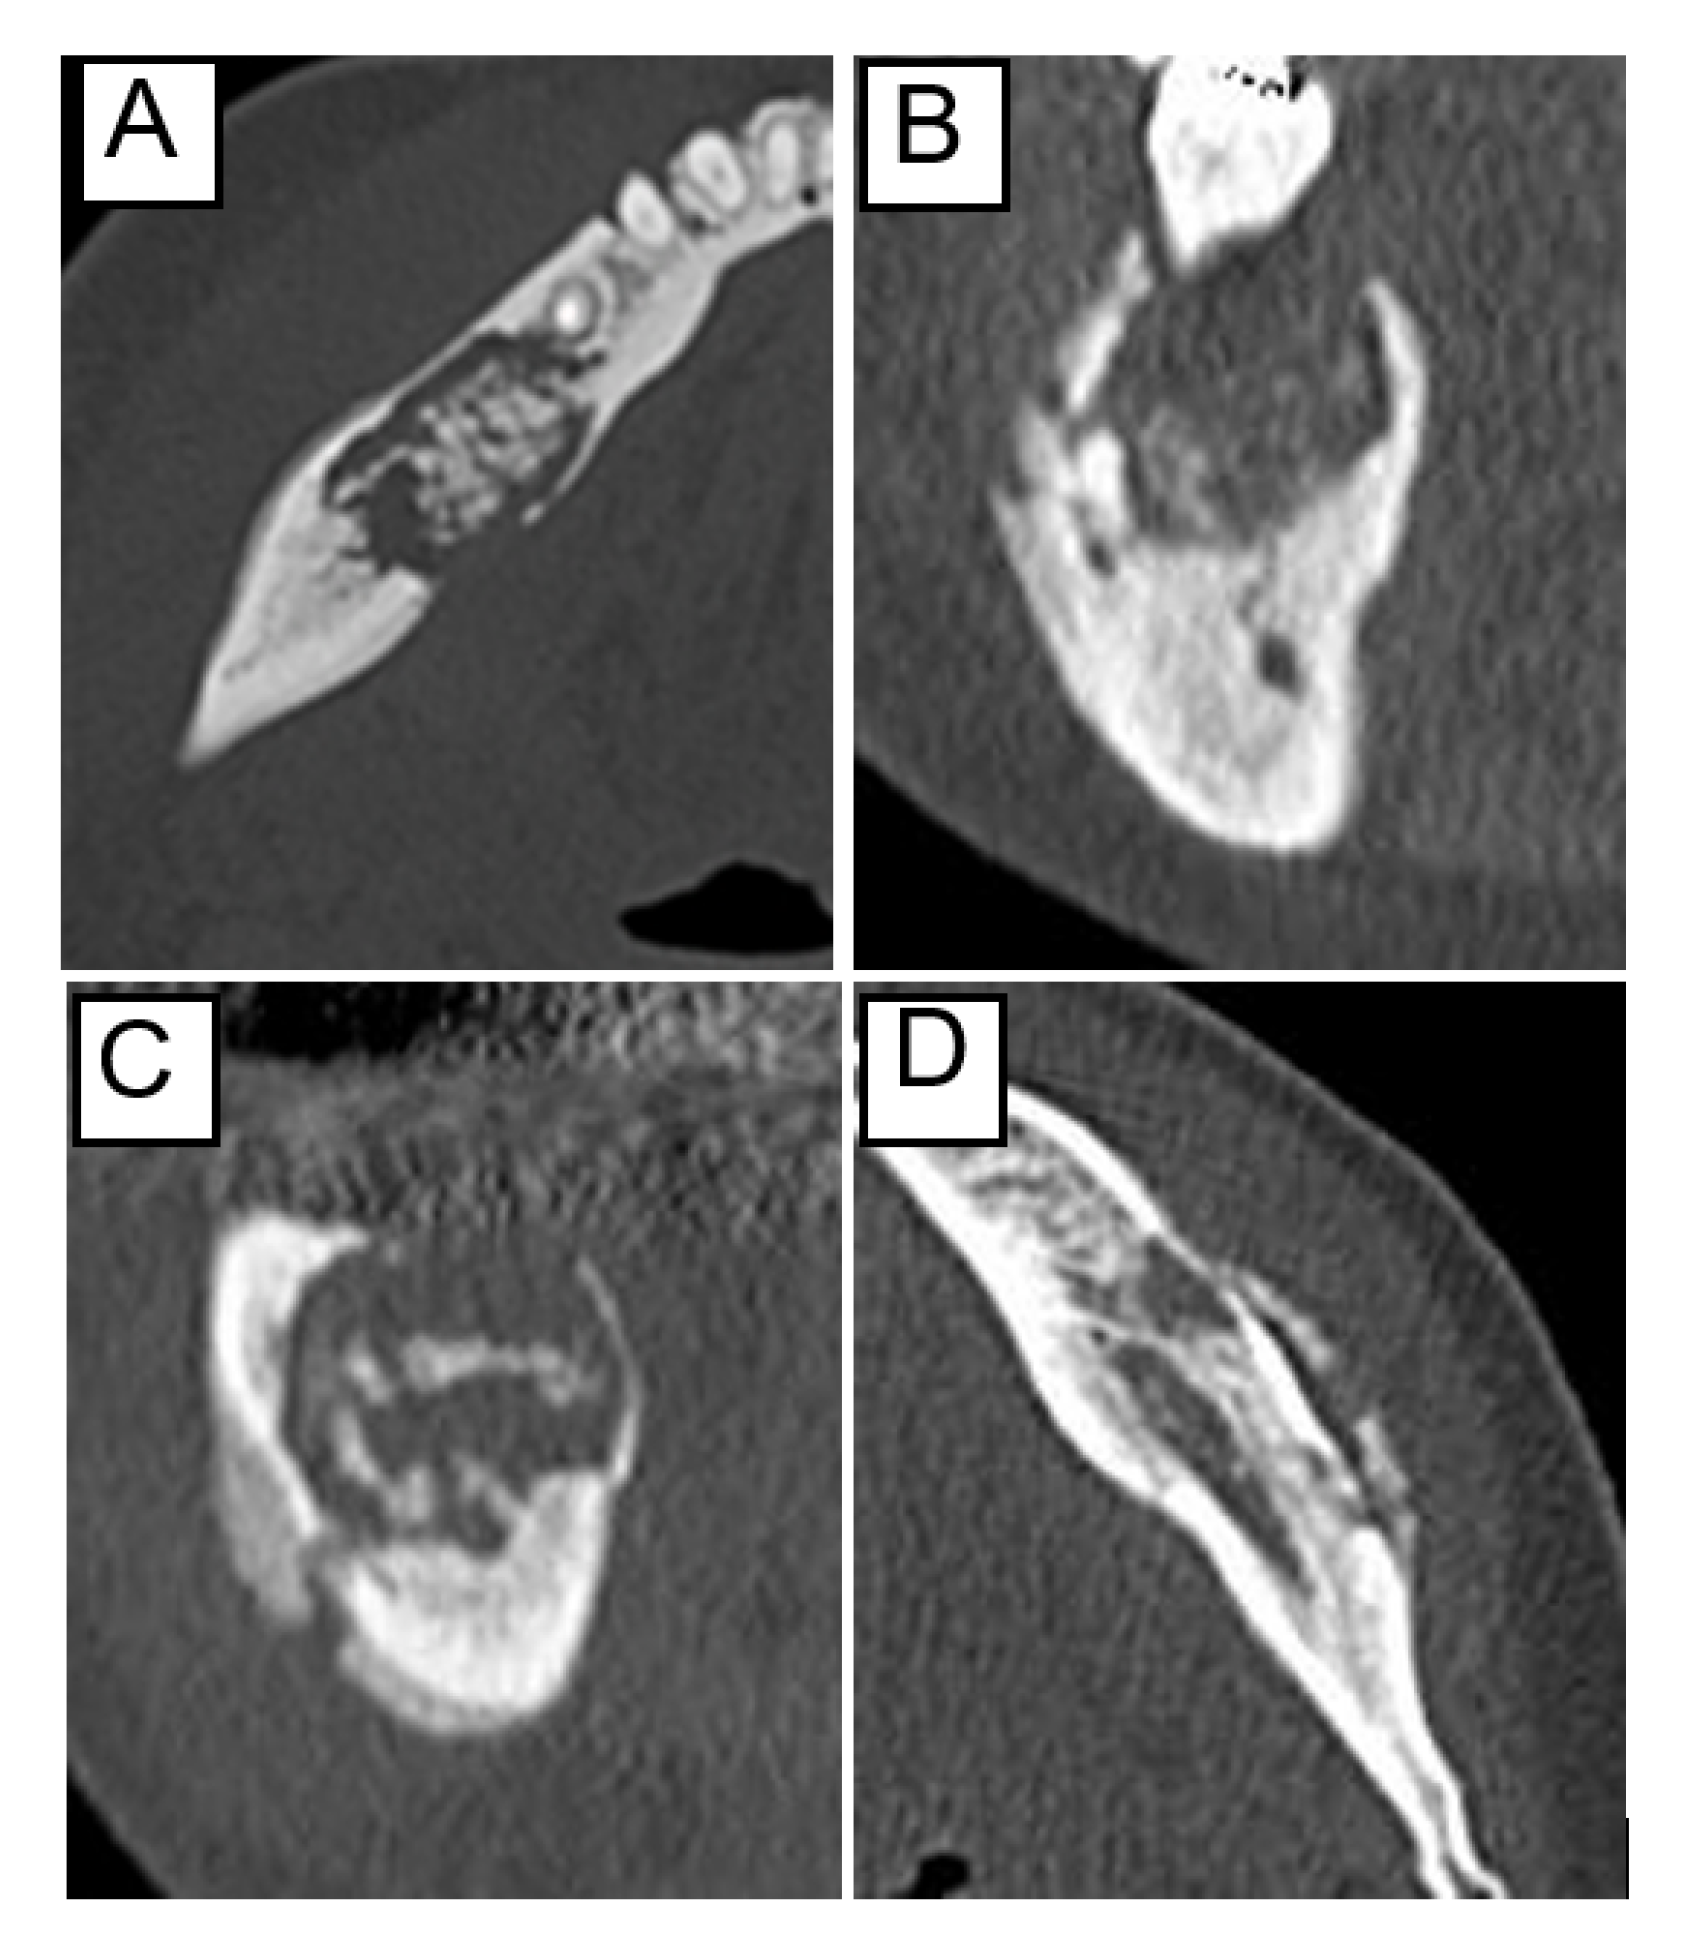

The site was defined as “anterior” from the incisor to the canine region, “posterior” from the premolar region, and “anteroposterior” included both sites. The separation of the sequestrum, the extent of the osteolytic lesion, and periosteal reaction were determined using computed tomography (CT) in bone mode. Regarding the sequestrum separation, those showing a radiolucent area between the necrotic bone and the surrounding bone in almost the entire area were classified as “with separation of sequestrum,” whereas the remaining were classified as “without separation of sequestrum” (Figure 1A). The extent of the osteolytic lesion was classified into “above the mandibular canal” and “including the mandibular canal” (Figure 1B,C). The lesions occurring in the anterior mandible were classified based on the hypothetical line of mandibular canal height. The periosteal reaction was classified into two types: with and without (Figure 1D).

Figure 1.

Examples of CT findings before treatment: (A) separation of the sequestrum, (B) osteolysis above the mandibular canal, (C) osteolysis including the mandibular canal, and (D) periosteal reaction.